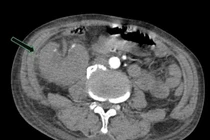

Bệnh nhân nguy kịch vì viêm thận đài – bể thận phải trên nền đái tháo đường tuýp II, xơ gan, ban xuất huyết và thiếu máu giảm tiểu cầu.

Trung tâm Y tế khu vực Tam Nông đã tiếp nhận và kịp thời cứu sống trường hợp bệnh nhân T.D.S (xã Tam Nông) nhập viện trong tình trạng nguy kịch do xơ gan tiến triển kèm viêm thận bể thận phải nặng.